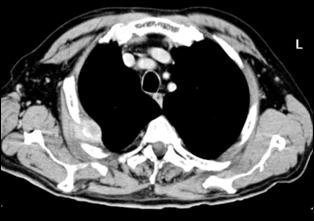

a. b.

c. d.

Figura 43. a,b,c,d) Imagini RMN de tumora vezicala.

Cele mai multe metasteze la distanta, provocate de tumorile vezicale maligne, sunt localizate in plamani si in oase. Diagnosticul acestora se face prin: radiografii toraco-pulmonare, radiografii osoase sau scintigrame osoase (evidentiaza metastazele osoase cu 9-12 luni mai devreme decat expresia evidenta a acestora pe radiografiile standard).

4.4. Rezonanta magnetica nucleara ofera cateva avantaje comparativ cu tomografia computerizata: tesutul tumoral este diferentiat mai bine de peretele vezical normal; examinarea se poate efectua in mai multe planuri; ganglionii limfatici se individualizeaza mai bine, putand fi deosebiti de vasele sanguine, si nu este necesara administrarea i.v. de substanta de contrast. In acelasi timp insa, miscarile pacientului pot induce artefacte neinterpretabile pe film, iar pacientii cu stimulatoare cardiace, clipuri vasculare metalice sau alte proteze metalice reprezinta contraindicatii pentru examenul prin RMN.

Cu toate progresele investigationale imagistice moderne, nici o tehnica de examen nu poate diferentia cu certitudine tumorile Ta de T1 sau T2 de T3a. Cel mai mare beneficiu diagnostic al tomografiei computerizate si al rezonantei magnetice nucleare consta in diferentierea corecta a tumorilor infiltrative, dar inca intra-organ (pana la T3a) de cele cu extensie extravezicale (T3b - T4a sau b). In privinta adenopatiei regionale, prin ambele metode se apreciaza ca ganglionii cu diametre mai mari de 1 cm sunt practic totdeauna invadati tumoral, in timp ce adenopatiile cu diametre mai mici considerate reactive, desi in cadrul acestora unele sunt totusi determinari neoplazice.